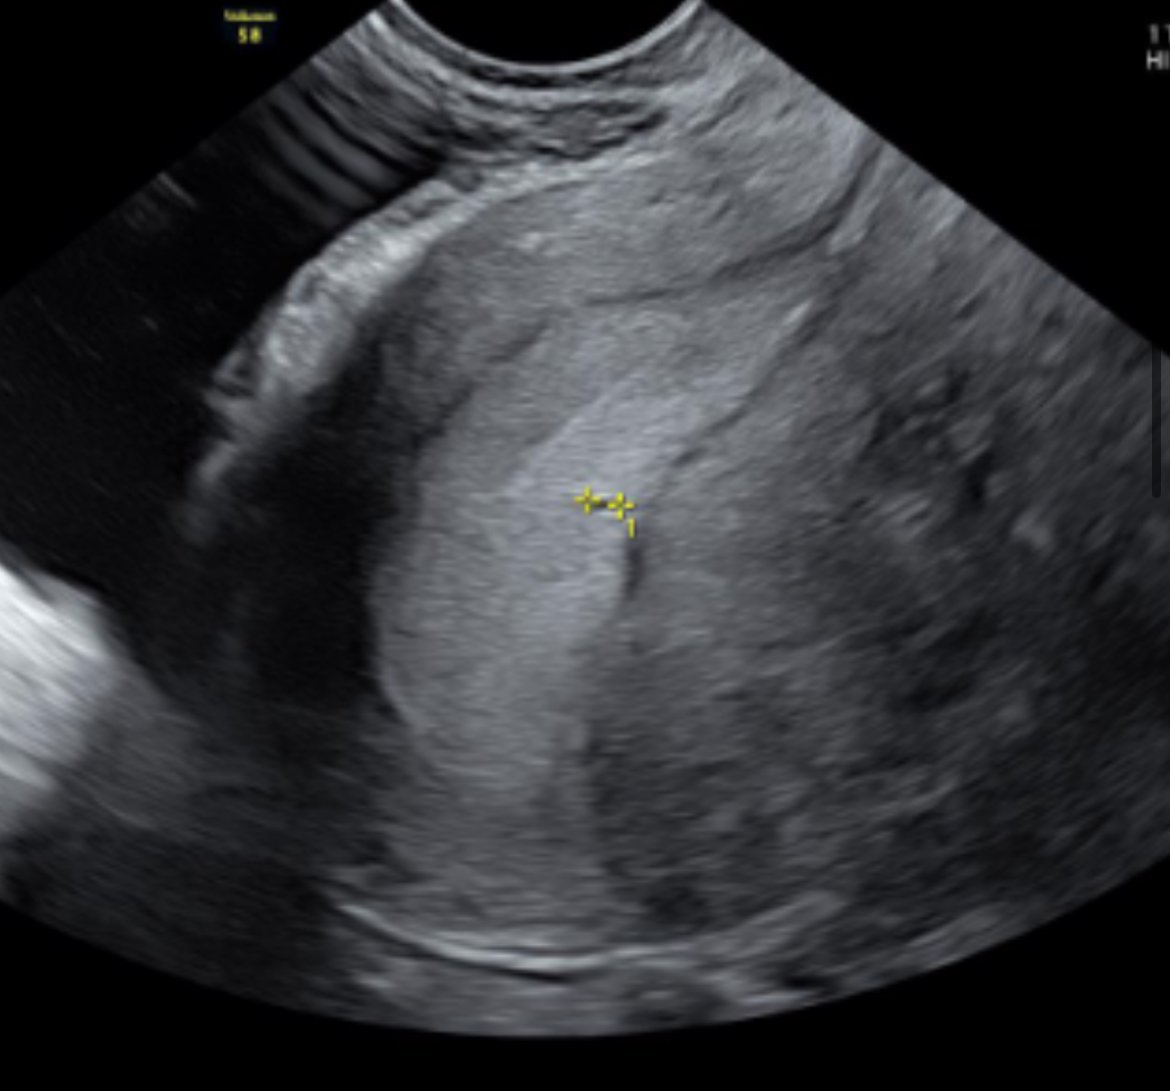

Иначе прикачвам и моята снимка от миналата година в 4г.с.+4, когато се видя точица.

Може би не се вижда много добре, но има бяло около нея. Тогава доктора ми го изтъкна това и каза, че ако наистина съм бременна това трябва да е околоплодното сакче.